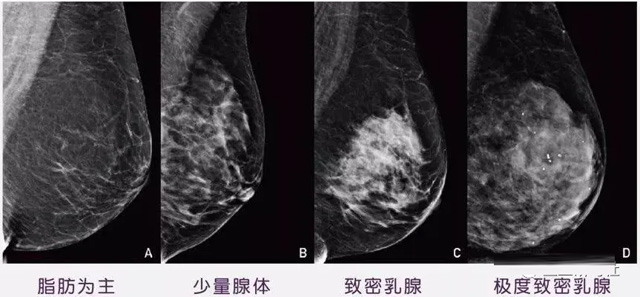

女性乳腺的自我檢查,特別是注意有小結節,腫塊,乳頭有液體滲出情況,需要通過乳腺DR,X光線,磁共振等影像技術檢查。胸的大小跟乳腺癌沒多大關係,乳腺的密度大發病率高一些,胸小脂肪少致密性大。更容易乳腺癌。這個還不能通過自我檢查來確認。致密乳腺組織看上去是白色或淺灰色需要通過乳腺X射線檢查。

乳腺X射線有輻射,40歲以下的女性沒有高危因素跟臨床特征,醫生都是不建議使用鉬靶檢查。乳腺超聲無創無輻射,對乳腺組織分辨率高。可以將乳腺腫塊從致密型乳腺組織中輕鬆查出來,多普勒模式檢查乳腺及病變,超聲小於1厘米的病灶非腫塊性乳腺癌檢出率低。超聲檢查結果依賴醫生水平和經驗,乳腺DR超聲推動乳腺超聲圖像的標準化,提高檢查的準確率。對乳腺組織內的細小鈣化灶, 從範圍、乳腺X射線形態以及分布特點上進行定性診斷。造影劑增強型乳腺X線攝影靜脈注射碘化造影劑結合乳房X線攝影。磁共振MRI對乳腺癌研究的深入對軟組織具有較高的分辨率等特點,在臨床上被廣泛認可。乳腺CT的探測器圍繞著乳房成像,無痛無擠壓,3D乳房圖像乳腺病灶的大小、數量、形狀、位置以及血管分布。一次掃描可創建多達兩千張投影圖像 。乳腺PET,適合普通人群和乳腺癌高危人群早期檢測,發現極早期微小病灶並明確定性。